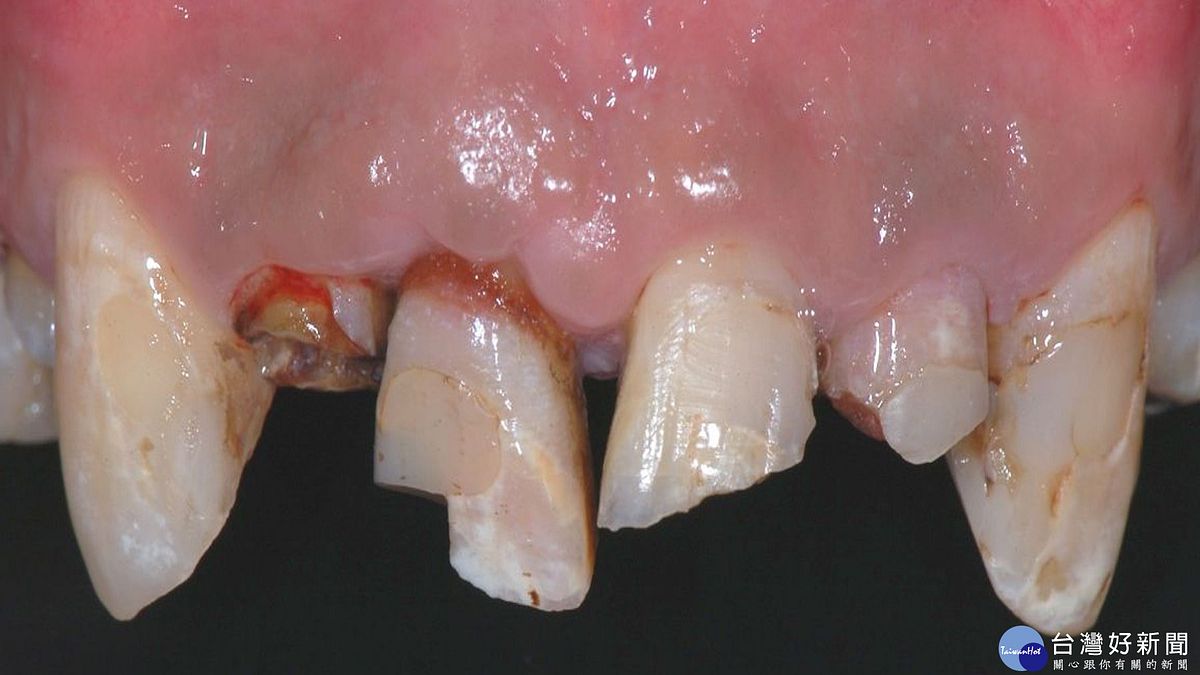

牙齒撞傷分成兩種,一種是整顆牙齒完整脫落,掉出齒槽骨;另一種是牙齒斷掉一部分,一部分還在口內。牙髓病科主治醫師賴曉錞說,整顆牙齒脫落,會因爲掉落口腔外的時間長短,及脫落牙齒的保存方式,讓治療方式和結果不同;牙齒斷裂,則視斷裂的情況和牙周韌帶是否受傷,來決定治療方式和預後。

若脫落的牙齒保存在適當的溶液中,並能在一小時內放回口內原位,牙齒有比較高的機率能保留下來,但後續需要定時且長期的追蹤。牙髓病科主治醫師賴曉錞認為,若牙齒脫落後保存不當、牙齒脫落時間過長、牙齒表面受損嚴重等,可能在追蹤的過程中需要做根管治療,甚至因為後續牙根發炎嚴重導致牙根吸收而需拔除。